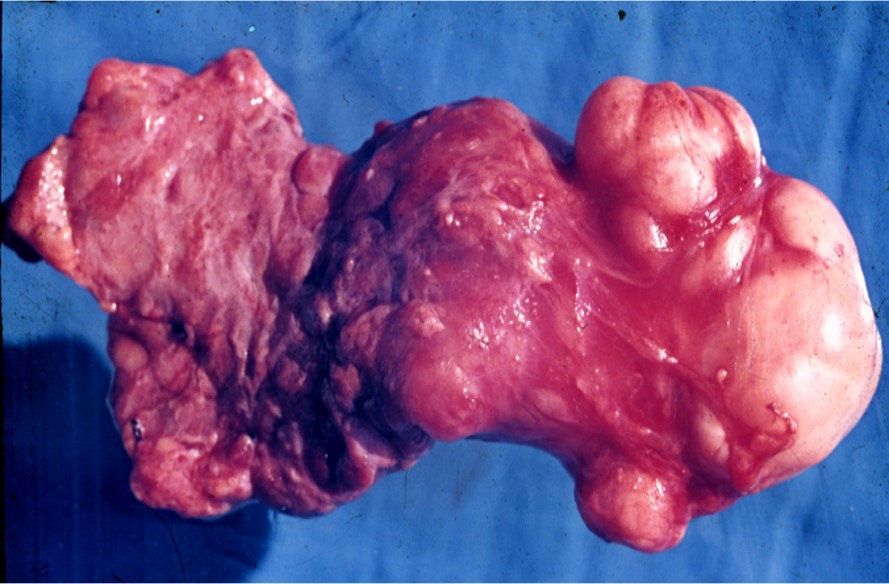

肉眼观察:

多为不规则结节状(图12.2-1)。剖面多为实性,灰白色或黄色;可见囊腔,内含透明黏液,有时见软骨样组织或角化物;多数肿瘤包膜完整。黏液样结构为主或小唾液腺不完整或无包膜。

图12.2-1 多形性腺瘤(肉眼)